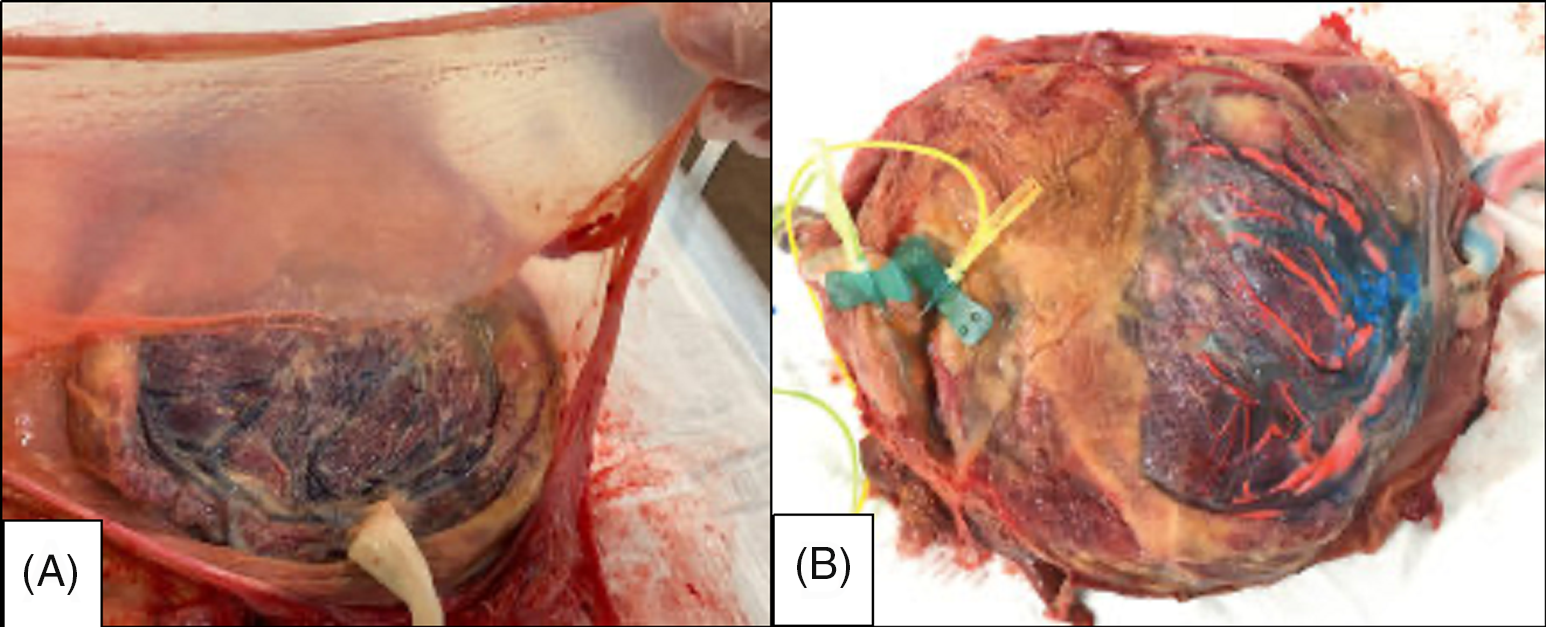

Macroscopic placental examination revealed that the placenta was composed of a single placental mass and two thin amniotic membranes without the interposition of the chorionic membrane, which formed an intertwin membrane at the middle of the placenta (Figure 4A). The placental vascular anastomoses could not be identified due to the thickening of the chorionic plate caused by the Breus’ mole that appeared in the late second trimester (Figure 4B).

Fig. 4. (A) Postpartum macroscopic evaluation revealed a thin intertwin membrane containing two amniotic membranes. (B) The placental vascular anastomoses could not be identified due to the thickening of the chorionic plate caused by the Bleus mole.

Histological examination confirmed that the intertwin membrane was composed of two amniotic membranes without a folded chorionic membrane, confirming the diagnosis of an MCDA twin pregnancy.